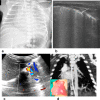

Cross-sectional imaging modalities like MRI and CT provide images of the chest which are easily understood by clinicians. However, these modalities may not always be available and are expensive. Lung ultrasonography (US) has therefore become an important tool in the hands of clinicians as an extension of the clinical exam, which has been underutilized by the radiologists. Reinforcement of the ALARA principle along with the dictum of "Image gently" have resulted in increased use of modalities which do not require radiation. Hence, ultrasound, which was earlier being used mainly to confirm the presence of pleural effusion as well as evaluate it and differentiate solid from cystic masses, is now being used to evaluate the lung as well. This review highlights the utility of ultrasound of the paediatric chest. It also describes the normal and abnormal appearances of the paediatric lung on ultrasound as well as the advantages and limitations of this modality.